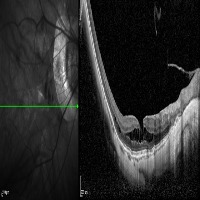

Medical Imaging Analysis: The "three-segment" model can be used by healthcare professionals for enhanced analysis of medical imaging, such as MRI or CT scans. It will help in identifying cleave classes, which can improve detection and diagnosis of potential issues in the brain, particularly those related to retina or neural connections.

Retinal Disease Diagnosis: Ophthalmologists could utilize the model to get help in diagnosing retinal diseases. It can help to identify any abnormalities by differentiating between the 'out', 'in', and 'retina' segments, enabling early detection of conditions such as retinal detachments or macular degeneration.

AI in Surgery: The model can be used to assist surgeons during complex neuro or eye surgeries. It can provide enhanced visualization, enabling real-time differentiation between various segments, leading to more precision in surgical procedures.

Medical Training and Education: The model can be used in medical learning settings, providing students with valuable visual learning material. It could serve as an advanced tool for the understanding of the retina and other segments of the brain or eye.